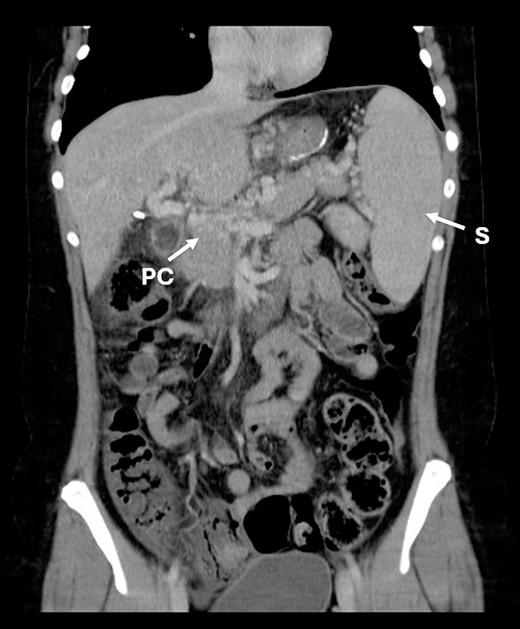

Three years after the bariatric surgery, during a routine imaging follow-up, the presence of portal cavernomatosis was detected (Fig. 1), along with significant palpable giant symptomatic splenomegaly, which subsequently led to thrombocytopenia and recurrent episodes of gingival bleeding. Furthermore, gastroesophageal varices had enlarged significantly, posing a high risk of bleeding and requiring recurrent endoscopic banding.

CT scan showing portal cavernomatosis and massive splenomegaly. PC, portal cavernomatosis; S, splenomegaly.

The findings of abdominal portosystemic collaterals, observed by upper gastrointestinal endoscopy and imaging studies, confirmed the presence of portal hypertension.